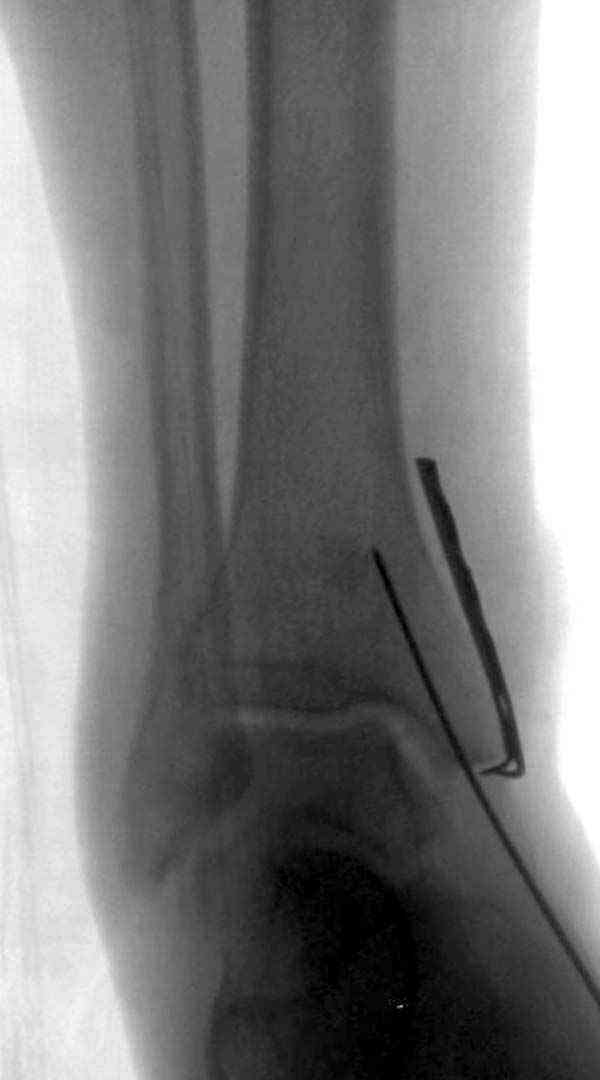

Нет первичных снимков, перелом очень низкий и под большим сомнением диагноз разрыва синдесмоза. Медиальная сторона отрепонирована на "хорошо" и, по-видимому, прорезание проволоки произошло во время операции. Без снимков трудно судить о высоте малоберцовой, а лодыжка находится в варусе. Лагирование получилось, но возле тонких шурупов передне-задний шуруп выглядит немного тяжеловато.

Медиальная лодыжка фиксируется каннюлированными лодыжечными шурупами перкутанно, а неточная репозиция (интерпозиция) является показанием к открытой технике. При больших вертикальных фрагментах нужны противоскользящие медиальные пластины.

Здесь несколько частных случаев: перелом голеностопа со сравнительными снимками и разрыв синдесмоза, а также медиальная Hook пластина.